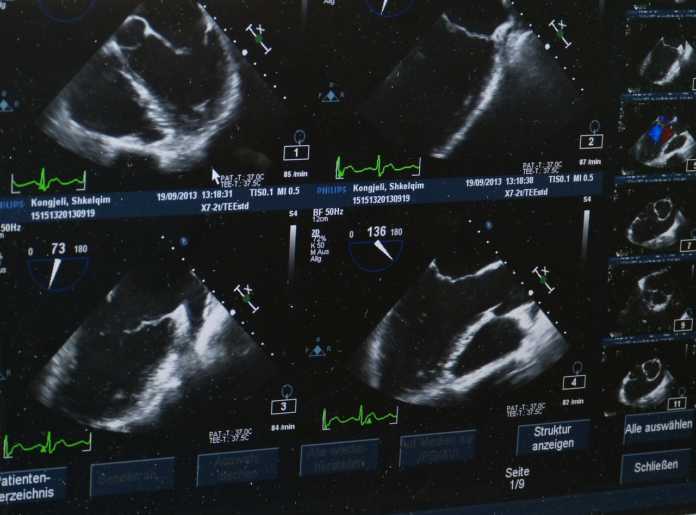

Jeden z aparatów USG trafi Centralnego Punktu USG, gdzie diagnozowani są pacjenci trafiający do szpitala zaraz po wypadku. Drugie urządzenie zostanie postawione w sali operacyjnej, aby w trakcie zabiegu można było sprawdzić, jak głęboko uszkodzone są narządy.

Dwa nowoczesne aparaty mają ułatwić diagnostykę pacjentów m.in. dzięki lepszemu obrazowaniu narządów wewnętrznych pacjenta. W Szpitalu Miejskim rocznie jest hospitalizowanych około 25 tys. osób.